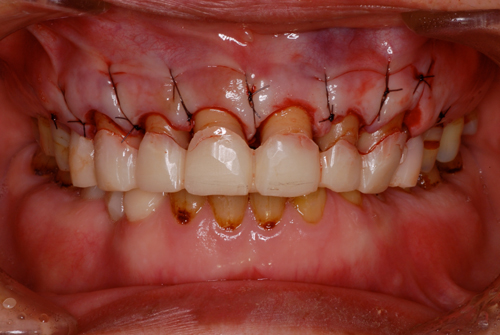

クラウンレングスニング

全体的な治療が必要なケース。

診断用ワックスアップを行い、クラウンレングスニング。